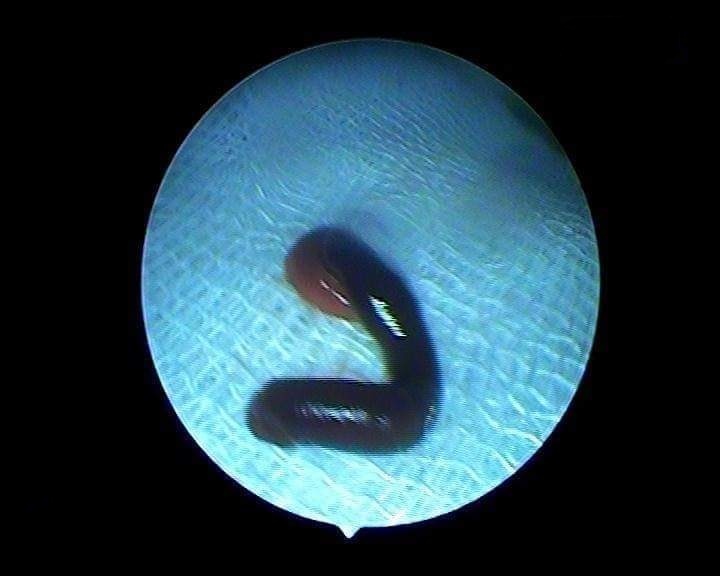

Con đỉa sống ký sinh trong mũi bệnh nhân N. Ảnh: Cắt từ clip.

Bác sĩ đã gắp ra một con đỉa đang hút máu và sống ký sinh trong hốc mũi bệnh nhân.

Ngày 25/5, Phòng khám Đa khoa Đoàn Kết ở huyện Quỳ Hợp (Nghệ An) đã gắp thành công một con đỉa suối dài khoảng 5 cm sống ký sinh trong hốc mũi bệnh nhân L.T.N. (24 tuổi, trú huyện Quỳ Châu, Nghệ An).